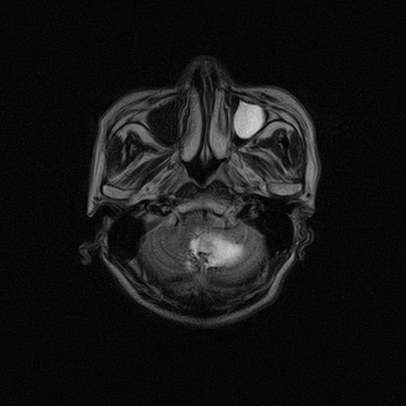

标题: MRI2064:少见病例。男性52,视力下降多年。 [打印本页]

标题: MRI2064:少见病例。男性52,视力下降多年。

四脑室区见混杂信号占位影,脑室系统扩张明显,临近结构显著受压称位,患者52岁,多考虑室管膜瘤可能性大

考虑第四脑室室管膜瘤并梗阻性脑积水;部分性空蝶鞍;左侧上颌窦粘膜下囊肿。

考虑第四脑室室管膜瘤【血供丰富血管母细胞瘤可能】并梗阻性脑积水;部分性空蝶鞍;左侧上颌窦粘膜下囊肿。

比较典型的脉络丛乳头状瘤并脑积水,鉴别小脑蚓部血管母细胞瘤。